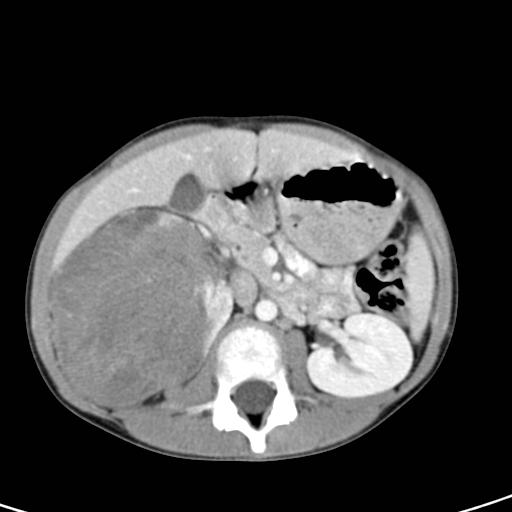

What's the Diagnosis?

Guess 1 / 5